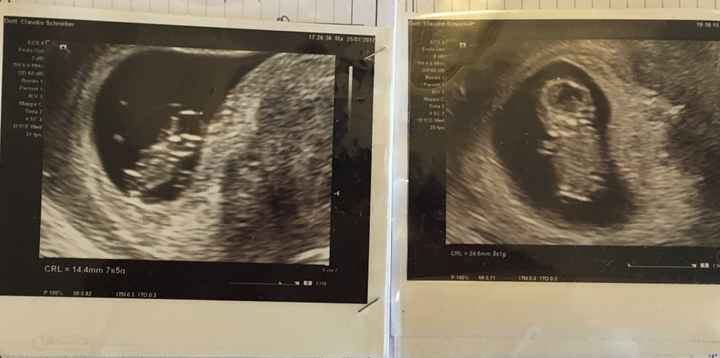

La prima ecografia a sinistra è della mia prima figlia che ora ha due anni, quella a destra l’ho fatta settimana scorsa. Dalla posizione a me parrebbe femmina anche la seconda, ma leggendo sembrerebbe che la placenta dovrebbe essere dall’altro lato.. insomma non ci ho capito molto!! Secondo voi? Le ecografie sono entrambe interne.